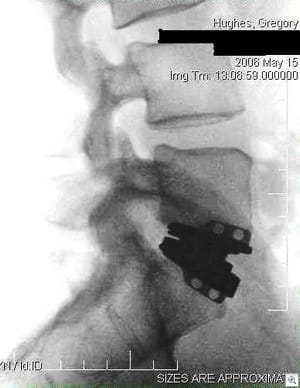

If you're not into x-rays or thinking about surgery and stuff like that, you can just skip this one. Many people have had me promise to show them pictures of the artificial disc that was implanted in me three months ago once I got them, so - well - here you go. This is a pretty amazing and relatively new (in the USA anyhow) area of medicine.

The Kineflex artificial lumbar disc is a three-piece metal-on-metal mechanical replacement, which is used to treat chronic and severe lumbar pain due to degenerative disc disease. It's in FDA trials right now, which makes me a bit of a guinea pig. It's not the kind of surgery you decide to do without a lot of serious thought and only after trying every other option. It replaced my natural disc, and now my severe back and leg pain that I lived with 24 hours a day for years is practically gone - and as a bonus I am a little bit taller than I was before the surgery. As I've said here before, I have my life back thanks to the doctors and the people that built this little device.

How'd they get it in there? The made an 8-inch horizontal incision just below my belly button (yep, they approach the spine from the front), spread the bones apart, removed the disc that was damaged, and put this new one in place.

You can click each image to view them larger-sized. I've removed any sensitive personal information.